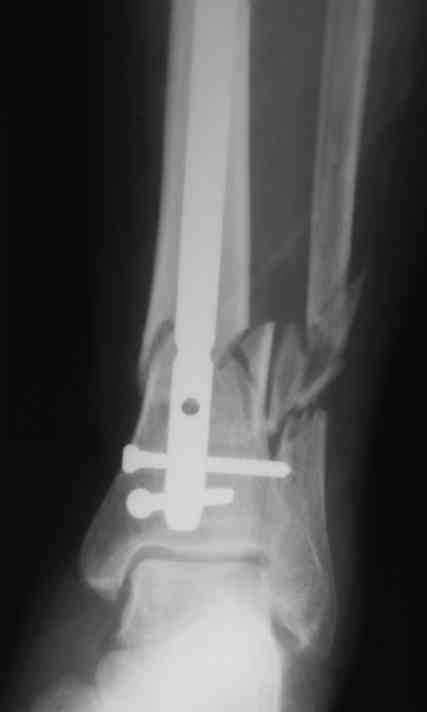

БИОС у пожилого пациента

Уважаемые коллеги!БИОС занимаемся недавно. Хотелось бы услышать Ваше мнение па данному клиническому примеру. Пациенту 74 года.

Выполнен открытый БИОС, обнаружен выраженный остеопороз, один из проксимальных винтов(самый верхний) и один из дистальных (нижний) "сорвались". В средней трети - косо-поперечный перелом (на фото не захвачен) с хорошей репозицией. Клинически фиксация переломов стабильна. Выполнить МОС малоберцовой кости не представлялось возможным из-за фликтен по латеральной поверхности голени.

4. Диаметр стержня - 11, нержавейка, производитель Санатметалл